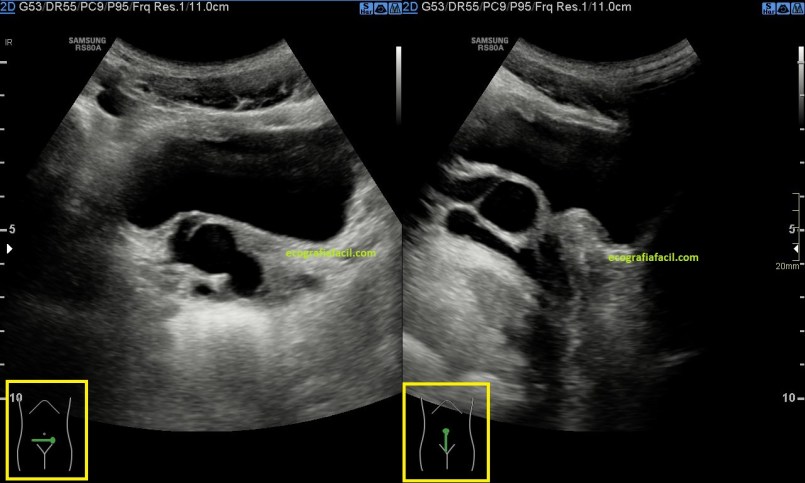

En la imagen 5 observa el estudio en ambos planos, tranverso y longitudinal de la vesícula seminal derecha y como la disposición ecoarquitectural se modifica sustancialmente en ambos planos, manteniendo semiología. Observa el pictograma.